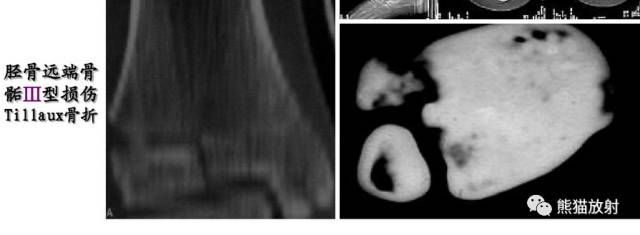

V型:骺板挤压性损伤(少见,多在晚期发生生长障碍时才能作出诊断)

Salter-Harris V型:由轴向压力导致的挤压伤,表现为骺板的明显扭曲或变窄。

第五型(V型) 骺板挤压性损伤,少见,占骨骺损伤的1%。由于严重暴力损伤造成,相当于骺板软骨的压缩骨折,有学者指出此型损伤只发生在一个方向活动的关节,如膝关节和踝关节。由于软骨细胞严重损伤破坏或来自骨骺营养血管广泛损伤,导致骺板早闭和生长停止。逐渐出现骨骼变形和关节畸形 ,但早期X线表现常常为阴性结果,多在晚期发生生长障碍时才能作出诊断。